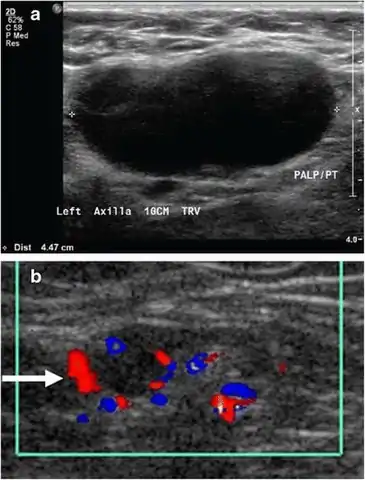

Doppler fetal monitor

Doppler fetal monitor Medical ultrasonography of a soft tissue lump, showing signs of a suspected malignant lymph node:[15]

Medical ultrasonography of a soft tissue lump, showing signs of a suspected malignant lymph node:[15]

- Doppler ultrasonography that shows hyperaemic blood flow in the hilum and central cortex and/or abnormal (non-hilar cortical) blood flow

- Increased focal cortical thickness greater than 3 mm

- Absence of the fatty hilum

Doppler ultrasonography can help distinguishing benign from malignant soft tissue lumps.[15] Power Doppler is useful in assessing tendon and joints inflammation such as paratenonitis.[16]